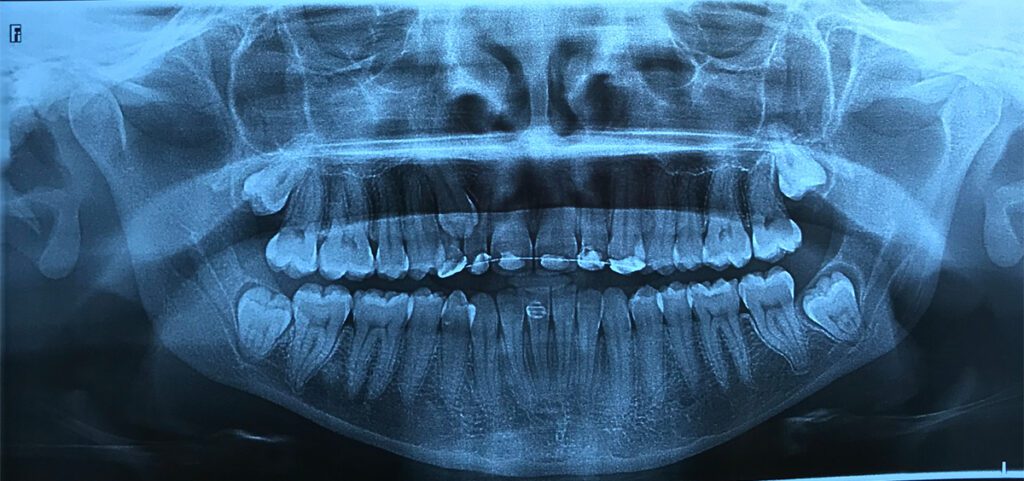

Estudios complementarios

A partir del análisis de la radiografía panorámica y los estudios tomográficos, se diagnosticó:

- Canino superior derecho (1.3) retenido

- Presencia de terceros molares retenidos